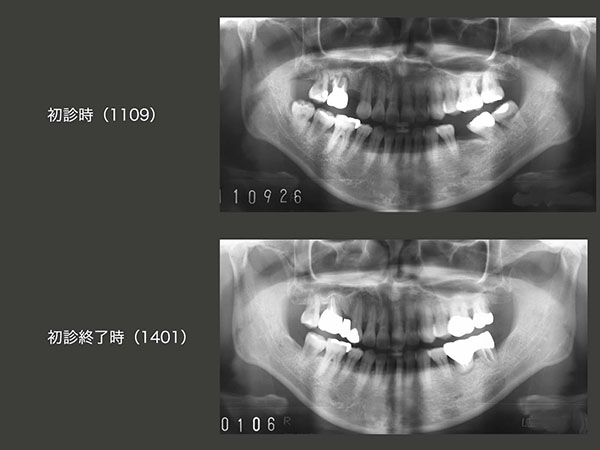

2011年11月初診,37歳女性.右上6が腫れたとのこと.この歯は歯周ポケットが5〜8mmあり,動揺も著しく保存不可能と診断した.患者さんは,歯科矯正のために第1小臼歯を4本抜歯しており,なおかつ右上5,左下6も失っていたが,今回さらに右上6が加わった.

上段に右上の経過を示す.まず2012年1月,右上に暫間義歯を装着した.さすがに右上3のクラスプが審美的に好ましくないとのこと.そこで左下8を抜歯し,右上6の欠損部に移植した.(12年2月)

つぎに下段に左下の経過を示す.左下8をドナー歯として抜去したため,前方に傾斜していた左下7のアップライトが可能となった.こうして左下6部のスペースを拡大したのち,今度は右下8を左下6部に移植した.

2014年1月,初診終了時の状態.左下6の移植歯は動揺がみられたため,左下7と連結固定した.同部に,フロスが入らないのが難点である.右上は,犬歯と移植歯との間に半歯分のスペースが残ってしまった.このままスペースを残したままという選択肢もあるが,患者さんは望まなかった.しかし,バージントゥースである右上3を削って,ブリッジにするのは抵抗がある.そこで,神奈川県で開業しているN先生に以前教えていただいた方法を採用した.すなわち,右上6(移植歯)は硬質レジン前装冠の近心にグルーブを細工し,セメント合着した.右上3は歯を一切削去せずに,補綴装置を接着性セメントで付けた.こうしておけば,何時か右上3とポンティックの部分の補綴装置は外れるが,その時また接着すればすむ.すごく良い方法であるが,年がら年中外れてしまっては困る方法でもある.実際,14年11月に1回外れたが,その後は何とか外れないでいる.